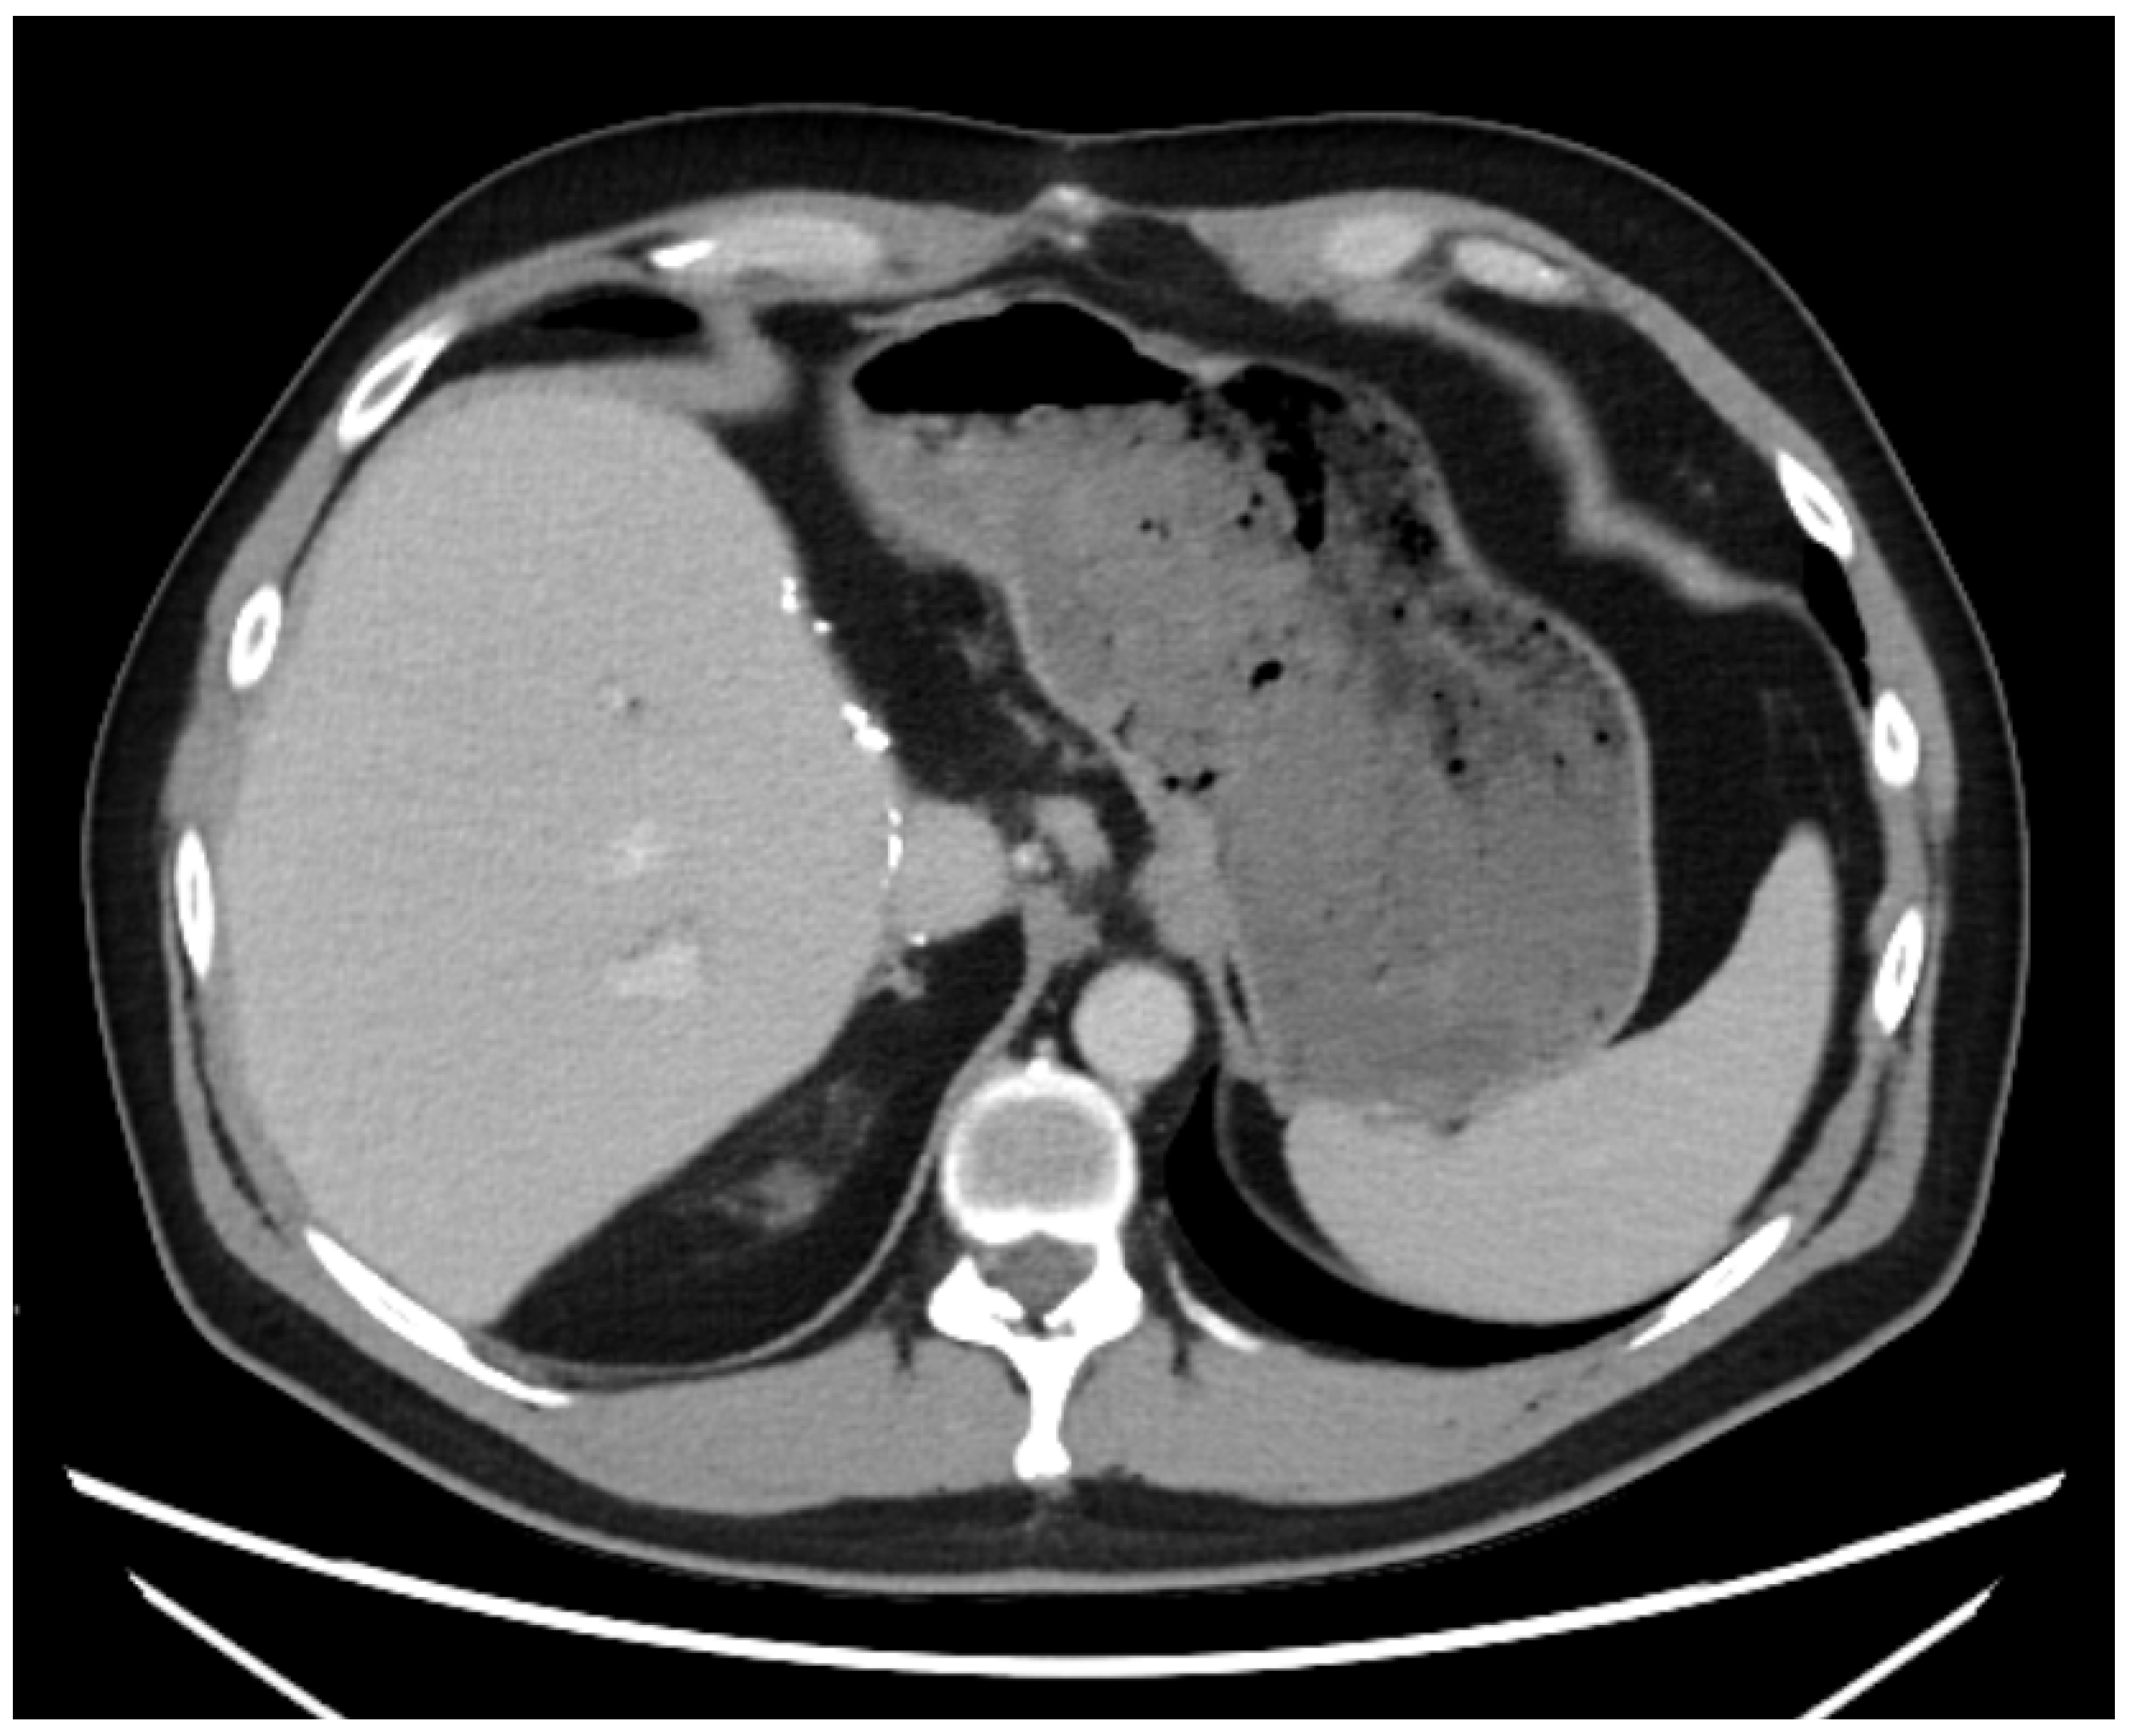

A 43-year-old man went because of persistent fatigue to the general practitioner. The diagnostic showed a large tumor within the central liver (see Figure 1a), which was biopsy-proven as a moderate-differentiated intrahepatic cholangiocarcinoma. An extrahepatic tumor spread could be ruled out (applying an FDG-PET-CT scan, see Figure 2a). Due to the invasion of the hepatic veins, which precluded a primary resection, chemotherapy with cisplatin / gemcitabine was initiated. The tumor showed a partial response (see Figure 1b). We decided to perform surgical exploration with the intent of an ex situ liver resection. Due to an invasion in liver segment VII, even an extended left trisegmentectomy was not possible. We performed an SIRT of both liver lobes resulting in a further, even metabolic (Standardized Uptake Value, SUVmean of the tumor in the initial PET scan: 7.3; SUVmean after treatment: 3.0), response of the tumor (see Figure 2a,b). The CA19-9 levels were always below the reference value. Twenty-two months after the initial diagnosis, the patient could be transplanted with a right living donor lobe from a friend. Histopathologic examination showed an intrahepatic cholangiocarcinoma with a maximum diameter of 6.3 cm. The tumor stage was ypT3, N0, L0, V0, Pn0, R0. Currently, 17 months after the LDLT, the patient is recurrence-free and in good clinical health (see Figure 3). The most recent CA19-9 level is 21.3 U/mL (reference value < 27.0 U/mL).

Figure 1. (a): Tumor load at the initial presentation of the patient. (b) Tumor load after cisplatin/gemcitabine therapy. Note the shrinkage of the left liver lobe.